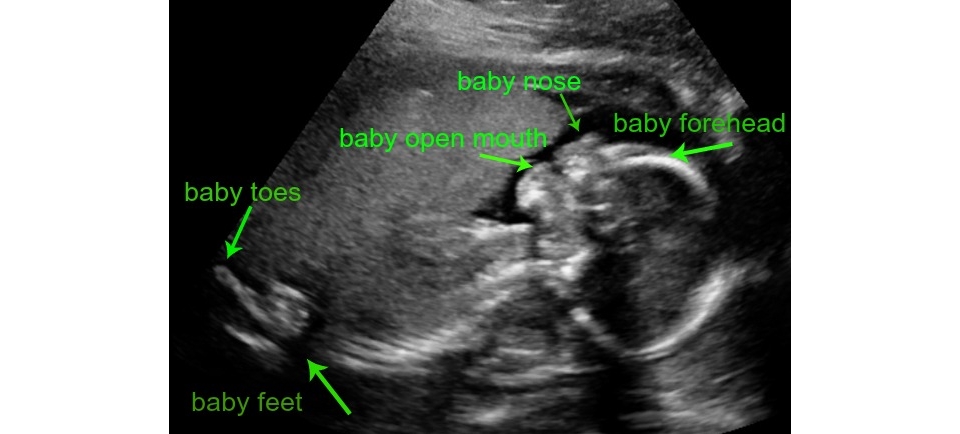

Today’s ultrasound appointment went great! We invited Jenn's parents to join usso it was a full viewing room and fun for us to share that together. Baby was being very shy for the camera, so the ultrasound technician took her time and was able to get measurements of baby and to check all of its organs for health.

The technician says the baby measures just under one pound, which perfect for being 20 weeks and 5 days along. Its heartbeat was beating at 156 beats per minute. At this stage baby is just under 11 inches long and we during the session saw it open its mouth and move its arms and legs. Jenn's favorite part was seeing its cute little feet which were crossed at the ankles. So darling! As baby grows and gets stronger Jenn can feel him/her more and more which is very exciting. This we will tour the hospital we plan to deliver at.